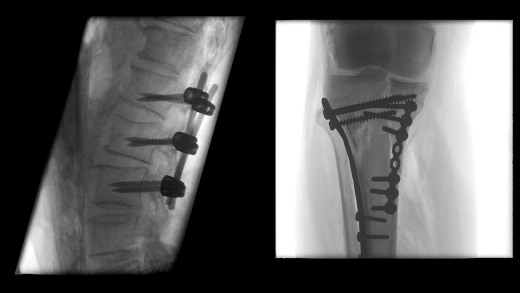

- Улучшенная цепочка визуализации матричного детектора с технологией CMOS: интеллектуальные алгоритмы автоматически регулируют яркость и контрастность, обнаруживают движение, улучшают края и оптимизируют визуализацию металла для улучшения изображения окружающих тканей

Больницы сталкиваются с ростом стоимости медицинского оборудования, поэтому им необходимо оправдать инвестиции. Cios Flow — это многофункциональная система, которую можно использовать в различных областях — ортопедической и травматологической хирургии, хирургии позвоночника, сосудистой хирургии и т. д. — позволяя повысить эффективность использования своих ресурсов.